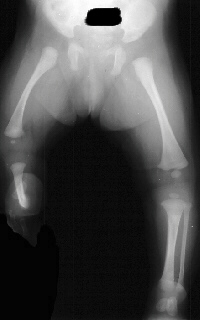

Soon after birth the infant was noted to have a severe deformity

involving the right leg and right foot. Examination of the right

lower extremity demonstrates shortening of the right thigh with

a 10 degree flexion contracture present in the knee. The knee

is noted to be in valgus. The foot is held in a position of severe

equinovalgus with absence of the lateral two rays. The patient

initially underwent a corrective tibial osteotomy and Boyd amputation

of right foot. The postoperative course was complicated by the

development of a nonunion at the osteotomy site.

Concurrent

anomalies of the ipsilateral femur common with congenital shortening

is seen in up to 60% of patients.

In

Congenital shortness of the fibula, Type IB - There is partial

absence of the fibula (30-50%) with the distal remaining portion

unable to function in ankle support.